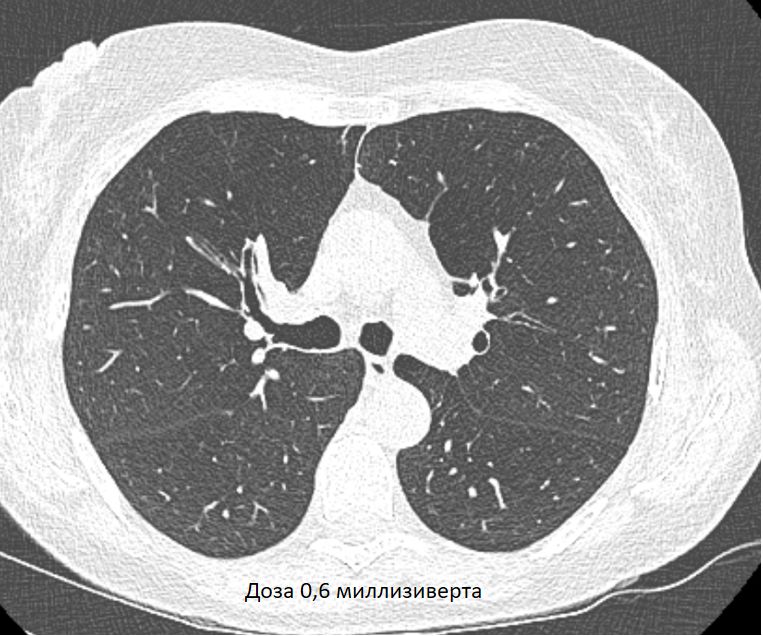

Изучение дозы излучения при рентгеновских исследованиях: визуализация